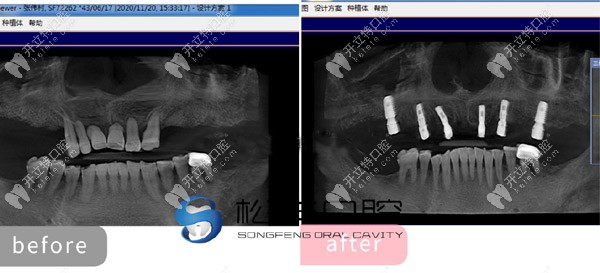

★ 上半口做了6顆即刻負重種植牙的CT片

上半口做了6顆即刻負重種植牙的CT片

通過這些真人的種植圖,可以看出。上海松豐口腔的種植技術(shù)真的不是吹的!但有人還質(zhì)疑上海松豐齒科正規(guī)嗎,這我可得來說道說道了!